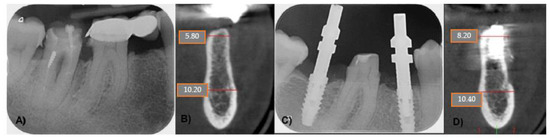

4.1. Patient No. 1

4.2. Patient No. 2

4.3. Patient No. 3

4.4. Patient No.4

4.5. Patient No.5

4.6. Patient No.6